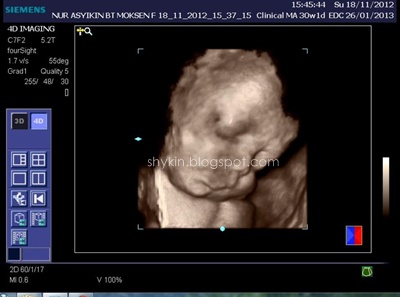

Dulu masa pregnant Fayyadh dan Fathi scan 2D je yang aku tahu. So, Kali ni konon-konon nak merasa la scan 3D. 4D pulak, aku pun ajak la suami pergi buat dekat klinik. Memang teruja la sebab 4D bole dengar sound dan tengok dia gerak-gerak dengan gambar coklat tu. Dah macam ada kat depan mata je baby padahal masih lagi dalam perut. Jakun jugak la haku... ngeh ngeh ngeh.

BTW aku buat dekat Klinik Sofea, Puchong Utama, scan 3d 4d murah la kat situ, RM80 sekali dengan CD. Setakat ini aku rasa kat KL ni tu yang paling murah. Lagi pula, tak payah buat appointment, walk-in terus je.

Proses scan dijalan oleh doktor yang bertugas masa tu. Okeyla jugak, puas hati sebab dia print hampir 10 keping result scan muka tu. Banyakkan??..

Jom view hasil 4dscannya. Yang ni aku printscreen dari VCD yang klinik tu bagi.

Bila kena usik bukannya dia bangun, dia amik tangan tutup muka.